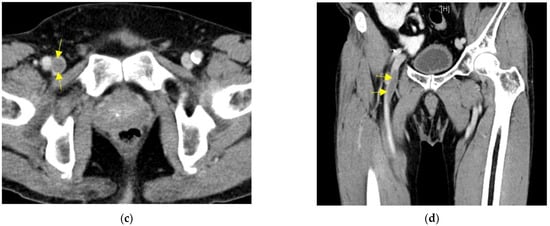

Following the third dose, he complained of exertional dyspnea accompanied with bilateral leg edema 26 days later, although no severe adverse effects were detected after the previous two vaccinations. His average creatinine was 1.06 mg/dL, and average trough levels of cyclosporin and everolimus were 42.9 ng/mL and 4.3 ng/mL in the past three months, respectively. The clinical details when symptoms presented are shown in Table 1. He had not changed the immunosuppressants in the past 6 months; however, his drug level of cyclosporin had become elevated to 64.9 ng/mL with slight elevation of creatinine in the month he presented symptoms, so we tapered the cyclosporin to 25 mg daily. Pulmonary perfusion scan (Figure 2a) showed one segmental perfusion defect lesion at left lung revealed as a pulmonary embolism. Also, venography study (Figure 2b) showed negative for deep venous obstruction in bilateral low extremities.

Figure 2.

(a) Pulmonary perfusion scan showed a segmental cold area in the lingual inferior segment of left upper lobe, the arrow shows the defect; (b) Venography study showed well visualization of the deep veins in the bilateral lower extremities with good drainage of radioactivity up to the inferior vena cava.